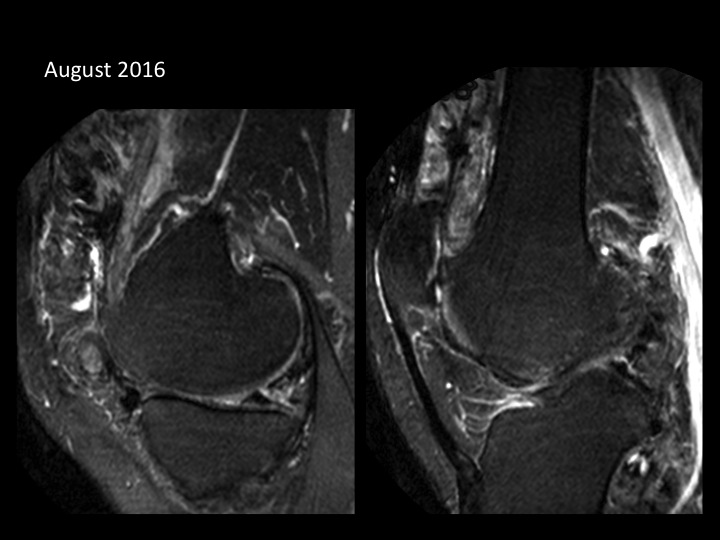

37M worsening pain and swelling, previous excision PVNS 2005 and 2007

In 2008 there was no degenerative cartilage loss and there was only focal nodular PVNS with large effusion. XRs from 2015 show new mild to moderate medial femorotibial and patellofemoral DJD. Todays MRI shows severe DJD which preferentially affects the medial compartment (there is also degenerative medial meniscal tear, new c/w 2008). There is diffuse, massive synovial thickening with innumerable dark signal synovial deposits. Ive not seen this sort of aggressive progression, from focal to diffuse PVNS. Have you?

pigmented villonodular synovitis ( RID3641 )